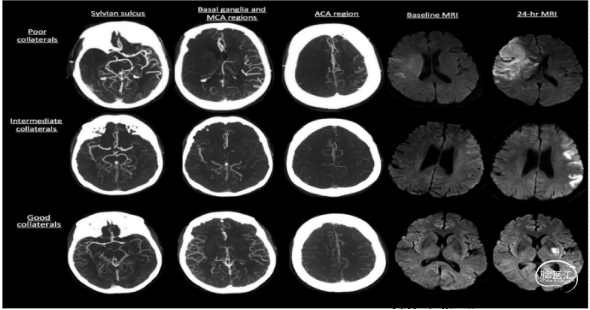

CTA评估侧枝循环

良好侧枝循环提高急性血管再通治疗获益率、降低出血转化的风险。共9个区域,包括外侧裂、ASPECT评分中的6个MCA区(M1-6)、基底节区、大脑前动脉区(A)

评分标准:

由于外侧裂部位是ACA-MCA-PCA软脑膜侧枝供血区,故赋值较高。0分:无显影;2分:显影血管较少;4分:显影血管相等或多于对侧动脉闭塞侧各区域血管与对侧正常血管显影对比,可分为三级:0分,无血管显影;1分,显影血管较少;2分:显影血管相等或多于对侧。总分20分:17-20 分提示侧支循环较好;11-16 分提示侧支循环中等;小于10 分提示侧支循环较差。